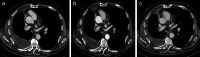

Treatment of malignant pleural mesothelioma (MPM) represents a highly unmet medical need. Here, we discuss the results and therapeutic potential of first- and second-generation immunomodulatory antibodies targeting distinct immune checkpoints for the treatment of MPM, as well as their prospective therapeutic role in combination strategies. We also discuss the role of appropriate radiological criteria of response for MPM and the potential need of ad hoc criteria of disease evaluation in MPM patients undergoing treatment with immunotherapeutic agents.